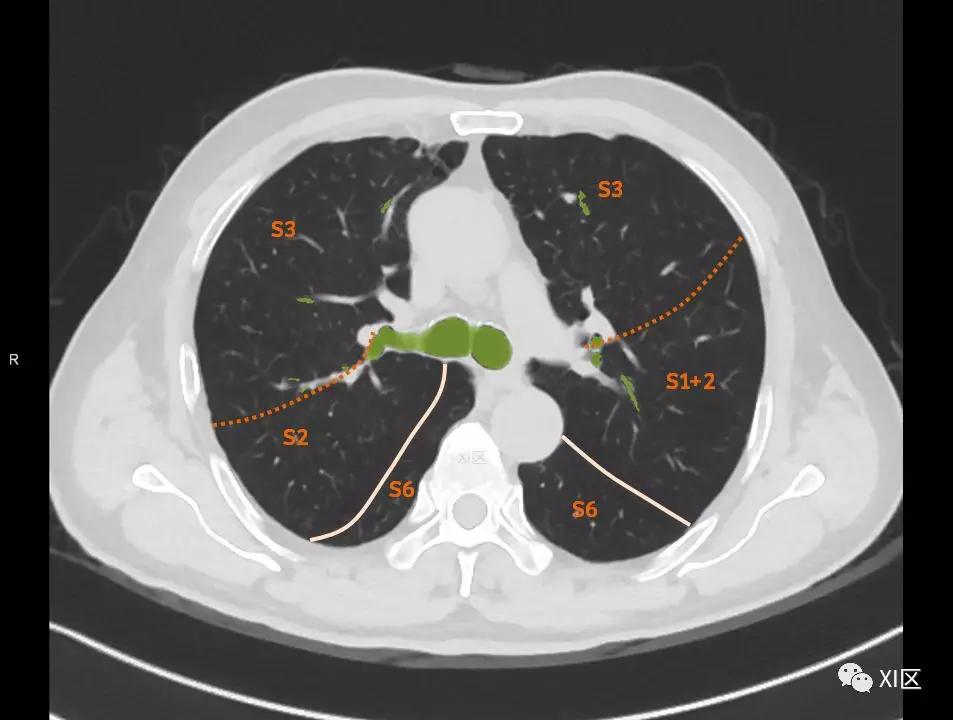

肺的断层分段示意图

在进行肺的分段时,可以上下观察浏览,沿着相应气管的走形可以更容易准确地进行分段。